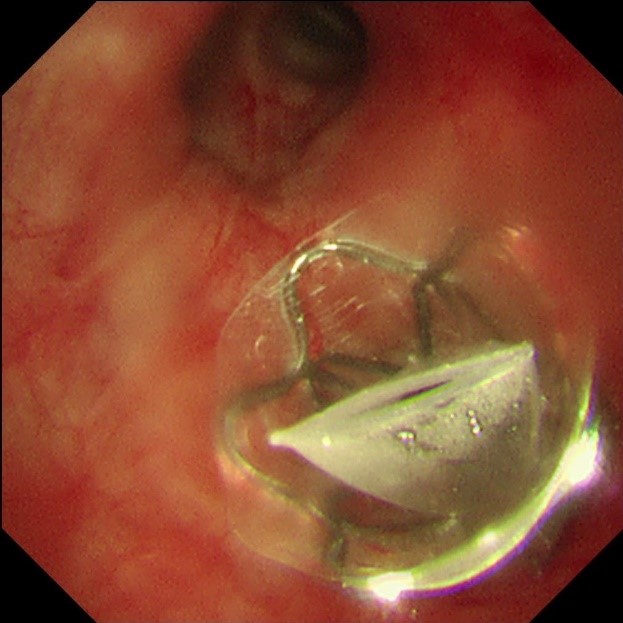

手术当天,蒋军红主任和曾大雄主任密切配合,用时30分钟便顺利完成手术。手术通过微创支气管镜介入,在高清内镜视野下,精准定位病变最严重的靶肺叶支气管,精准植入一枚微型支气管内活瓣(EBV-TS-5.5),术中实时验证活瓣开合状态良好,通气单向引流功能正常。